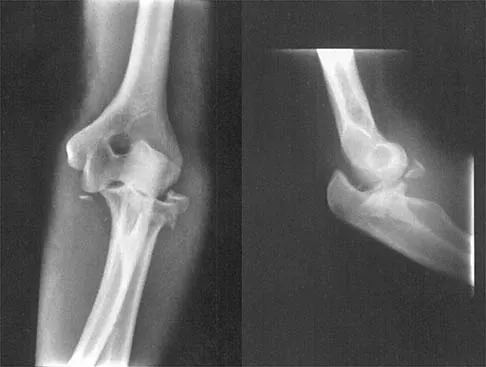

Figure 3 shows the radiographs of a 32-year-old man who fell 12 feet onto his outstretched arm and sustained a fracture-dislocation of the elbow. Initial management consisted of closed reduction of the dislocation. Surgical treatment should now include repair or reduction and fixation of the

Explanation

The radiographs show fractures of the coronoid and radial head. The medial collateral ligament has been avulsed from the ulnar insertion, and there is a valgus opening on the medial side. The lateral collateral ligament is always disrupted in elbow dislocations and fracture-dislocations that occur secondary to falls. This is known as the terrible triad injury (dislocation and fractures of the coronoid and radial head); it has a very poor prognosis because of its propensity for recurrent or persistent instability and late arthritis. The principle in treating this injury is to repair all of the injured parts or protect them with a hinged external fixator until they heal. Norris TR (ed): Orthopaedic Knowledge Update: Shoulder and Elbow. Rosemont, IL, American Academy of Orthopaedic Surgeons, 1997, pp 345-354. Kasser JR (ed): Orthopaedic Knowledge Update 5. Rosemont, IL, American Academy of Orthopaedic Surgeons, 1996, pp 283-294.